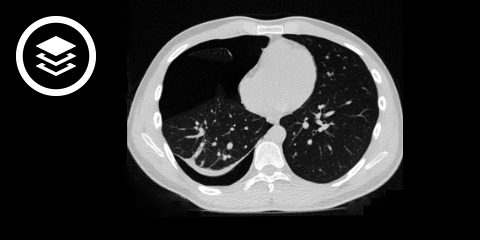

CT-Thorax

Die native Computertomographie ist insbesondere indiziert bei unklarem Befund im Röntgen-Thorax, Polytrauma-Patienten sowie bei komplizierenden Befunden (z.B. Hämatopneumothorax).

DICOM-Modelle können auf Mobilgeräten leider nicht angezeigt werden.

- Bildquelle DICOM-Viewer: Datensatz freundlicherweise zur Verfügung gestellt durch die Klinik für diagnostische und interventionelle Radiologie, St. Vinzenz Hospital Köln